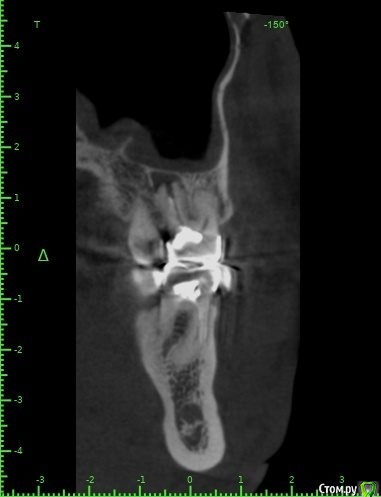

Raystom Опубликовано 20 февраля, 2021 Поделиться Опубликовано 20 февраля, 2021 Обратилась пациентка с неприятными ощущениями в области зубов 26, 27, во рту эти зубы показались мне темнее остальных, на КТ видна вот такая красота. Каков план лечения в таких ситуациях? Попробовать отделить пазуху от грануляций или просто удалить и после лечения ЛОРа идти на закрытие ОАС? Как после восстанавливать кость? И какие временные промежутки. Понимаю, что многие скажут при таких вопросах передать другим, но это не мой вариант. Мб есть литература по подобным случаям? Ссылка на комментарий

Карен Аванесов Опубликовано 22 февраля, 2021 Поделиться Опубликовано 22 февраля, 2021 Обратилась пациентка с неприятными ощущениями в области зубов 26, 27, во рту эти зубы показались мне темнее остальных, на КТ видна вот такая красота. Каков план лечения в таких ситуациях? Попробовать отделить пазуху от грануляций или просто удалить и после лечения ЛОРа идти на закрытие ОАС? Как после восстанавливать кость? И какие временные промежутки. Понимаю, что многие скажут при таких вопросах передать другим, но это не мой вариант. Мб есть литература по подобным случаям?Аккуратно удалить, убрать грануляции, инструментально уточнить есть ли сообщение с пазухой (Думаю что нет), если и есть, коллаген, и лунку ушит. Динамичный контроль. Ссылка на комментарий